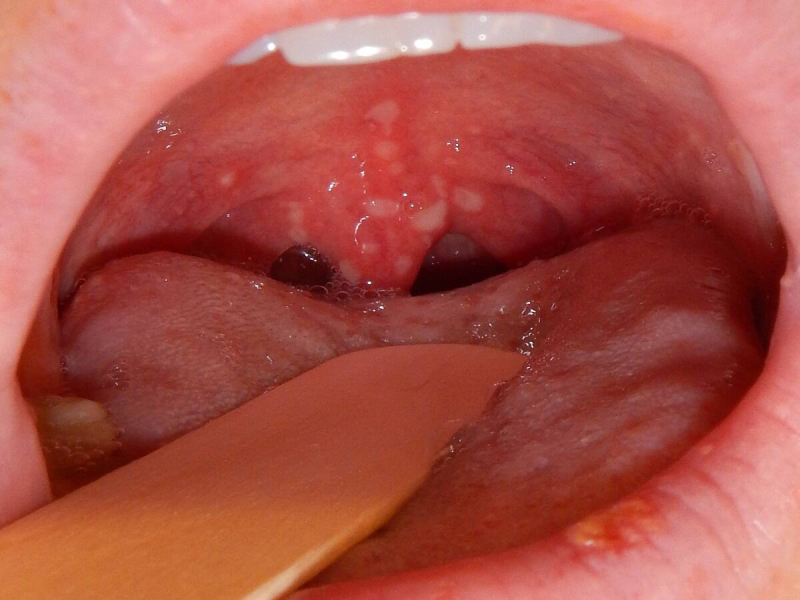

Tumors & Cancers

Discover symptoms & explore medicines and treatment options. Also read expert health articles about symptoms, the latest research, medicines and alternative treatments for every disease and medical condition.